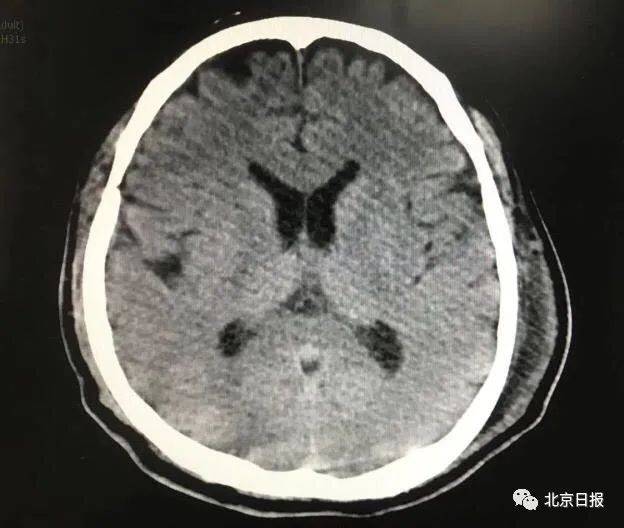

为验证该纳米胶囊(nRTXCXCL13)对继发性中枢神经系统淋巴瘤的治疗效果,研究人员首先构建了可形成稳定脑转移的人源非霍奇金淋巴瘤细胞株。在免疫缺陷小鼠中腹腔注射淋巴瘤细胞2F7七周后,部分小鼠形成了继发性中枢神经系统淋巴瘤,将脑转移瘤组织取出进行单细胞分离培养,最终获得2F7-BR44细胞株。腹腔注射该细胞株7周后或尾静脉注射1-2周后,该细胞株可在全部小鼠中形成继发性脑瘤。同时,该细胞株表面重要受体CD19、CD20、CD22和CXCR5的表达水平与野生型淋巴瘤细胞保持相似,能被利妥昔单抗有效识别和清除。